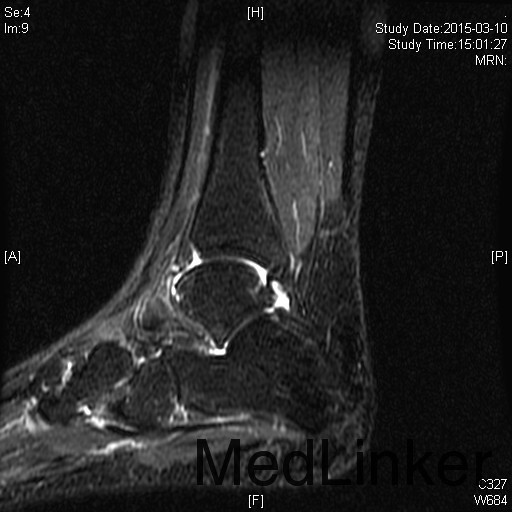

左踝扭伤后肿胀疼痛伴活动受限半年

查体:左腓肠肌萎缩,左踝轻度肿胀。左踝关节ROM较对侧降低,以背伸活动受限最明显。距腓前韧带处未及明显压痛。左踝内、外侧关节间隙压痛(+)。ADT(-),外侧应力试验(-)。左下肢肌张力正常、感觉正常。 辅检:MRI示“左踝关节积液”

诊断:左踝关节创伤性滑膜炎 治疗:左踝关节镜下滑膜清理、胫骨前缘成形

随访:患者术后即刻踝关节活动度恢复正常,2周恢复正常行走。 讨论:踝关节扭伤很常见,扭伤后会发生各种各样的情况。此患者扭伤后继发了滑膜炎,并伤及了关节软骨。这种情况应进行关节镜手术治疗。此外,核磁共振对关节疾患的诊断也是有限的,关节镜才是黄金标准。